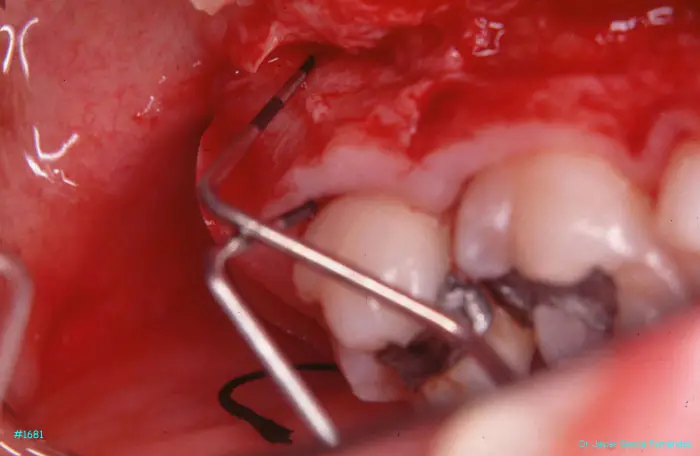

Atlas of Surgical Techniques in Periodontics. Chapter IV. Atlas de Técnicas Quirúrgica en Periodoncia

image 193